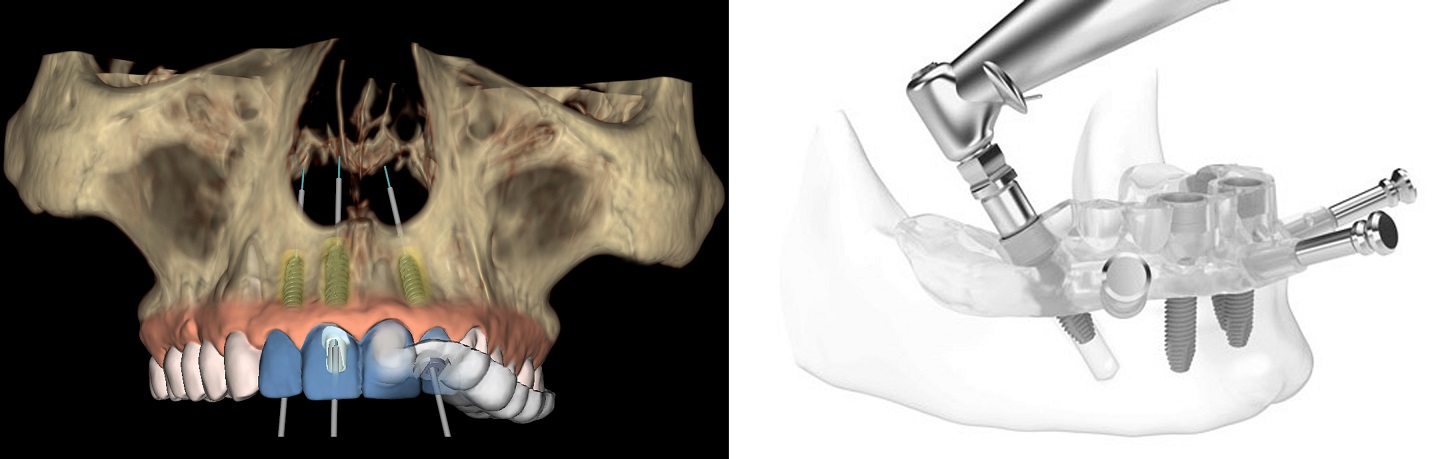

1. We do all implant placement by ‘Robotic Guided Surgery’ for precise, painless, bloodless, stitchless, and fast recovery.

Advantages of Computer Guided Robotic Implant Surgery:

We first create a virtual plan using the implant planning software (Nobel Guide) and also give options of Computer Guided Surgery.

1. No stitches and no gum opening surgery is required.

2. Very fast surgery through the small hole.

3. Less Painful surgery.

4. Very Less post-op discomfort.

5. Flapless procedure – Fast healing.

6. Precise implant placement.

7. No chances of trauma to surrounding vital tissues.